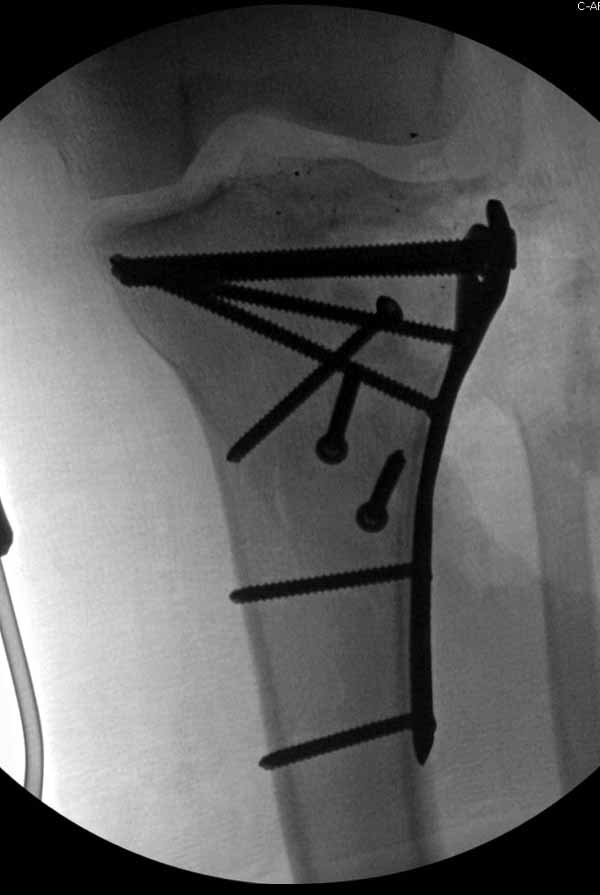

Клиника и течение заболевания похожи на однокамерную кисту. Больная молодая, желательно сохранить собственную головку. Надо спешить с операцией, иначе скоро произойдет перелом через тонкую стенку. Во время операции внутри будет пустота и небольшое количество жидкой крови.

Из всех перечисленных методов подходит вариант пластики аутокостью и усиление (арматура) шурупами. Основная задача сохранить интактную медиальную стенку и латеральный кортекс. Доступ передне-латеральный, но надо работать спереди шейки через небольшое окно в 10-15 мм. Фиксацию надо проводить между медиальной тонкой стенкой головки и латеральным кортексом. Каннюлированные шурупы 6.5 мм очень грубые и могут разрушить остаток стенки. Фиксировать надо кортикальными шурупами 3.5 мм, которые создадут мостик и арматуру в шейке. Провести по периметру шейки 4, и в центре пару шурупов. Во время операции и при манипуляции соблюдать осторожность, в любой момент может наступить стресс перелом. Заранее надо заказывать длинные шурупы!